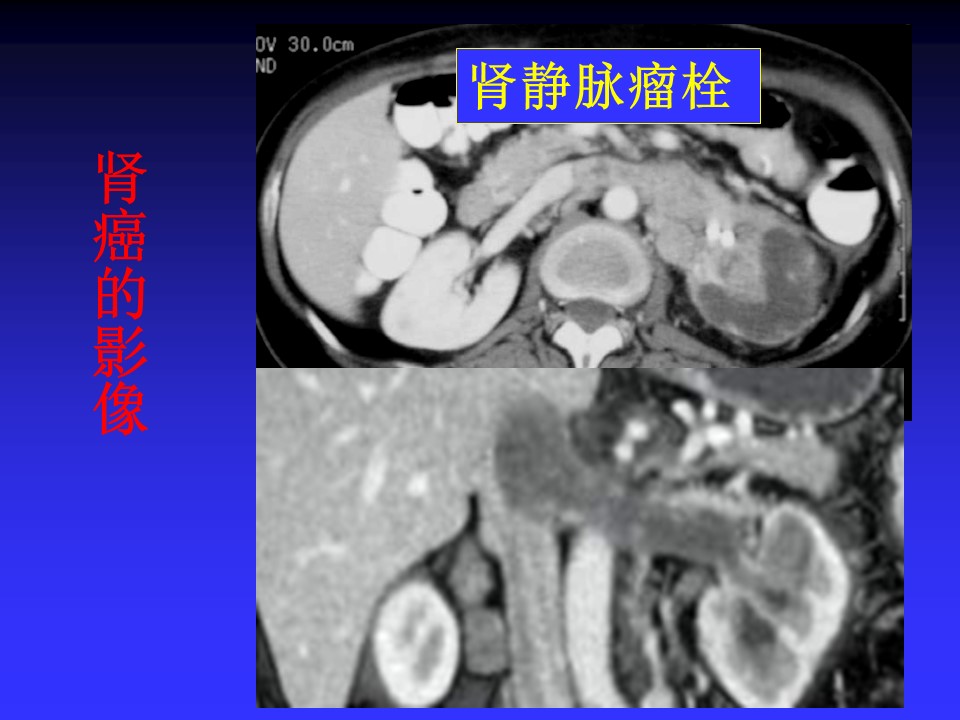

“肾脏肿瘤的影像诊断PPT” 的相关文章